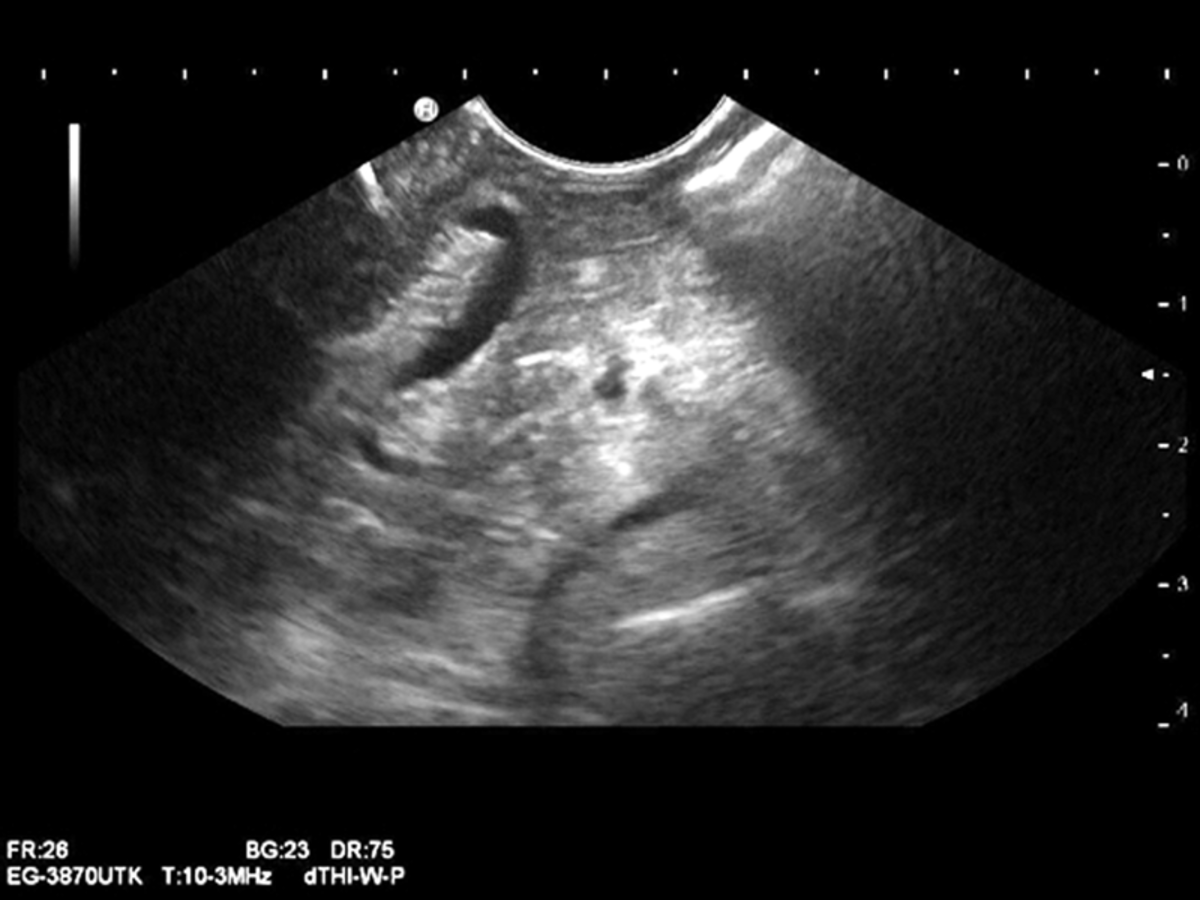

Der „Blick“ mit dem Echoendoskop geht mit einem Winkel von 120° schräg nach vorne. Der „Blick“ mit dem Echoendoskop geht mit einem Winkel von 120° schräg nach vorne. © Leineweber T. Hamburger Ärzteblatt 2018; 72: 30-32 © Hamburger Ärzteverlag, Hamburg

Im Vergleich zum Duodenoskop (links) hat das Echoendoskop (rechts) allerdings auch einige kleine Nachteile: Der „Blick“ geht mit einem Winkel von 120° schräg nach vorne – dadurch ist eine optimale Einstellung nicht immer möglich. Zudem ist die Spitze des Geräts länger, was die Manövrierfähigkeit einschränken kann. Im Vergleich zum Duodenoskop (links) hat das Echoendoskop (rechts) allerdings auch einige kleine Nachteile: Der „Blick“ geht mit einem Winkel von 120° schräg nach vorne – dadurch ist eine optimale Einstellung nicht immer möglich. Zudem ist die Spitze des Geräts länger, was die Manövrierfähigkeit einschränken kann. © Leineweber T. Hamburger Ärzteblatt 2018; 72: 30-32 © Hamburger Ärzteverlag, Hamburg